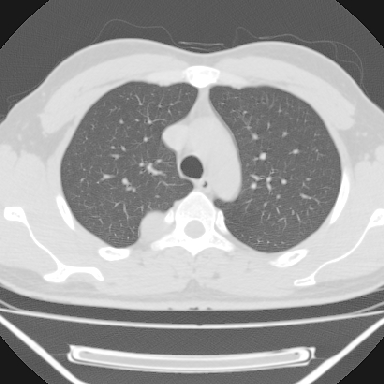

m 30 右胸痛10年

右上后纵隔脊柱旁类圆形肿块,边界光整,与胸腔呈钝角,首先考虑来源于肺外,神经源性肿瘤(神经鞘瘤可能大,神经鞘瘤)

右上后纵隔旁软组织肿块影,与肺界面光滑,与胸壁呈钝角相交,提示肺外病变。位于肋骨下缘,边缘清楚,呈三角样指向与右侧椎间孔,但并示进入椎间孔;与对侧神经根对比,属同一走行方向。

考虑后纵膈良性肿瘤,神经源性肿瘤可能大。

鉴别:胸膜来源肿瘤。影像表现虽有肺外征象,但无胸水等相应佐证;再者,病史前10年,超长,与胸膜肿瘤不太吻合。

建议:再次查体,问清疼痛部位,如为1~2个肋间痛则神经源性肿瘤可能大,如疼痛较弥散,不按肋间分布,则可能为后纵膈其它来源肿瘤。

右上后纵隔脊柱旁类圆形肿块,边界光整,与胸腔呈钝角,首先考虑来源于纵膈,神经源性肿瘤可能大。

右上后纵隔脊柱旁见长椭圆形肿块,边界光整,与胸壁呈钝角。周围骨质未见异常。

考虑、1、后纵隔神经源性肿瘤;

2、不除外单发胸膜间皮瘤。